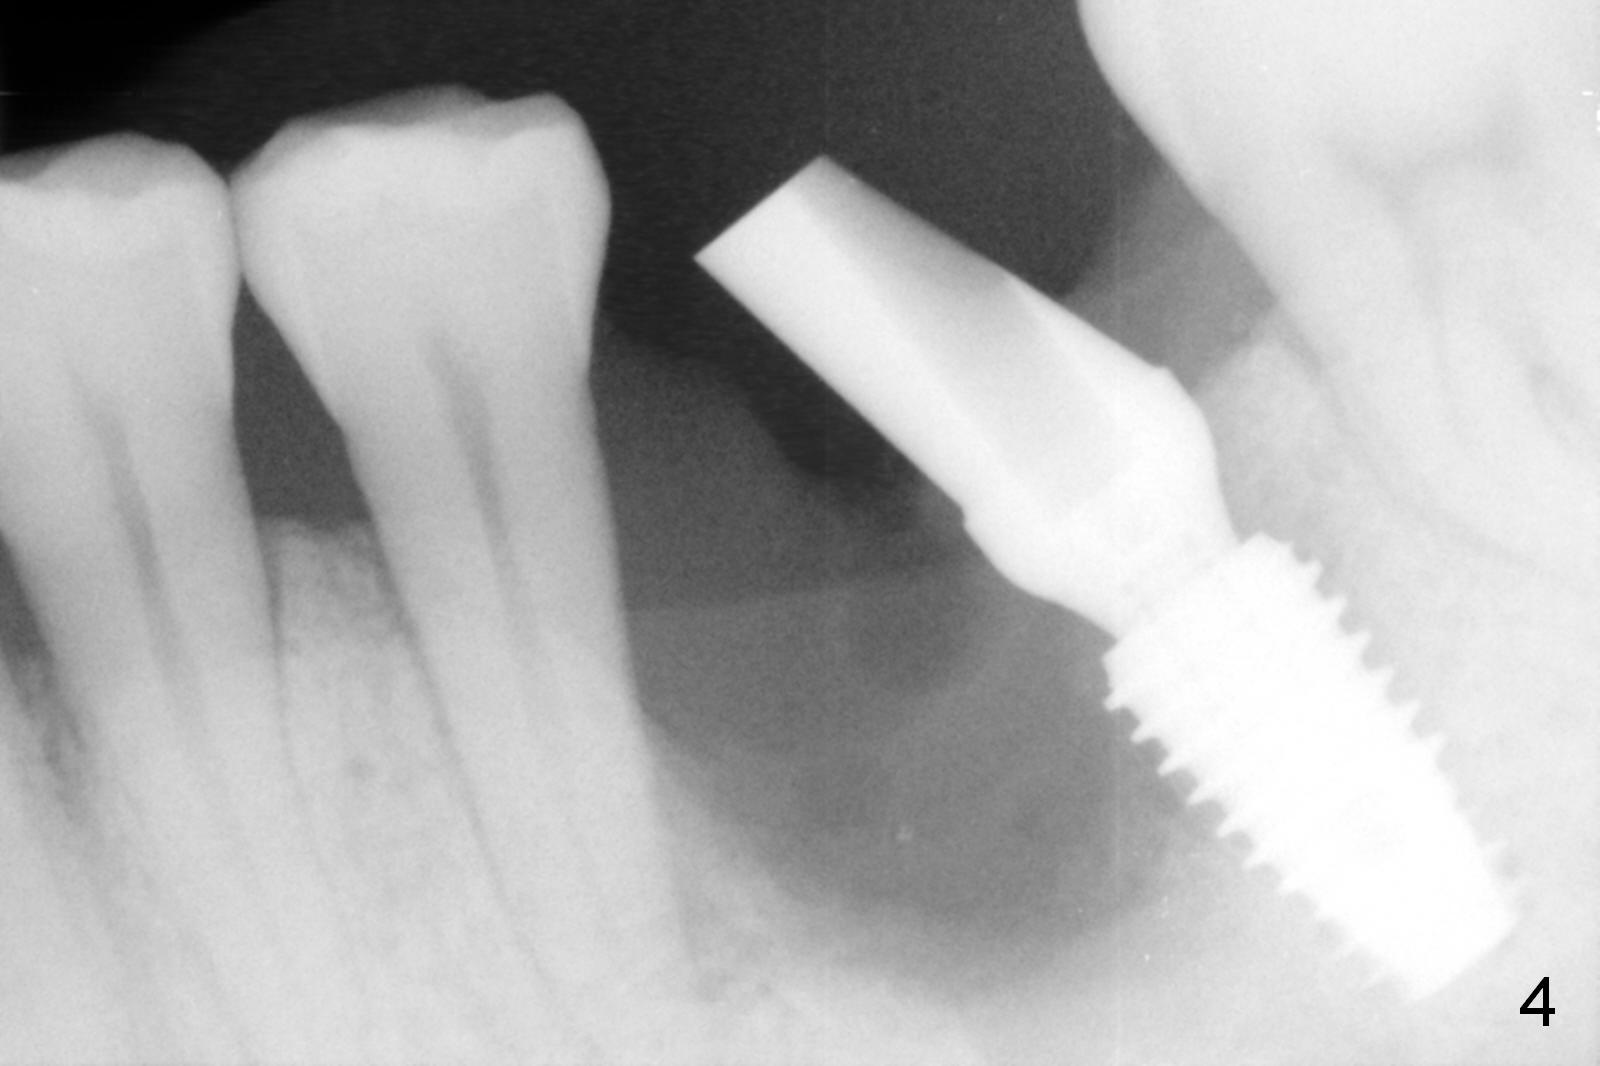

Considering the severe bone loss in the meisal socket, socket preservation is indicated if immediate implant is not feasible.  Preop exam shows that the mesiobuccal gingival recession (Fig.1 MB) is not as severe as the mesiolingual one (Fig.2 ML).  Because of oozing from the mesial socket, buccal envelop incision is made with flap raising to increase visibility.  Probably due to periodontal infection, pain control is difficult.  Osteotomy buccal to the Inferior Alveolar Canal proves to be risky.  In addition, osteotomy in the mesial socket is more difficult than the distal one (Fig.3).  Once the osteotomy depth is determined relative to the superior border of the Inferior Alveolar Canal (4 mm), the osteotomy depth increases by 2 mm.  A 5.5x10 mm implant is placed with insertion torque ~ 35 Ncm (Fig.4); a 15 ° angled abutment (5.5 mm in diameter, 4 mm in cuff) is placed mesially.  Then the abutment is turned lingually favorable for restoration (Fig.5), the remaining socket is filled with allograft/Osteogen (*) and Collagen Plug.